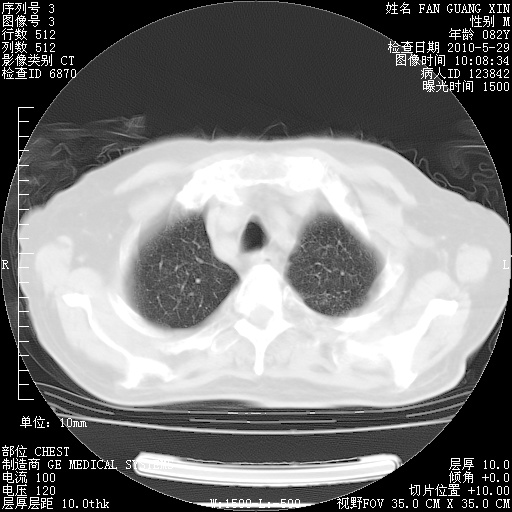

再治疗10天后的肺部CT 纵膈窗

阅读此次胸部CT,肺间质渗出性改变较入院时有吸收。目前从体温、白细胞、中性分叶明显增高,肯定存在细菌感染(发生医院感染哦,若无消化道及泌尿系统等感染的依据,肺部感染可能大)。若你院头孢哌酮舒巴坦钠耐药率较高,同意你的方案,若48小时体温仍高,可考虑使用碳青霉稀类抗菌药物,同时可予超声雾化、注意滴数时加大液体量。白蛋白33.30g/L较低哦,需加强营养等支持治疗。